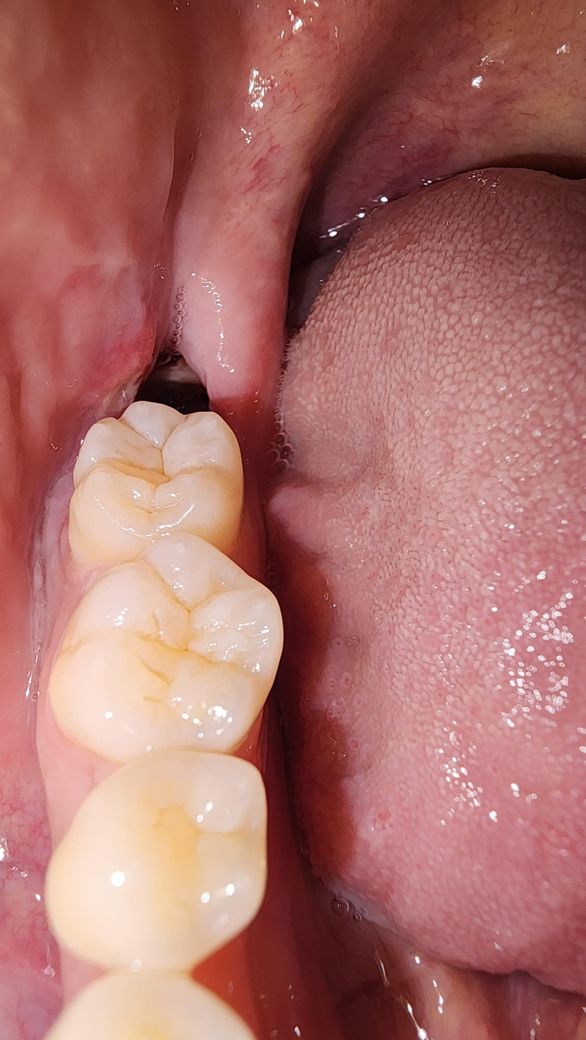

사랑니 발치 5일차인데 회복이 잘 되는겅가요?

사랑니 발치 5일차입니다

3일차부터 발치부위가 살짝 시린느낌이 나더니

어제는 밥 먹으면서 약간의 통증이 있었습니다

오늘도 식사 후 통증이 좀 있었지만 집에와서 진통제를 섭취하니 괜찮아졌는데 혹시 문제가 있는건가요?

혈전도 안보이고 뻥 뚫려있습니다

• 1번 째 사진

사진상으로 보면 발치한곳은 잘 아물고 있는것같습니다. 치아 빠진 구멍은 최소 한달은 지나야 메꿔질꺼에요.

발치 후 5일 차라면 약간의 통증은 느껴질 수 있으며 구멍은 시간이 지나면서 자연스레 메워집니다.

구멍이 닫히려면 1~2주는 걸립니다 발치후 주의사항 잘 지켜 생활하시고 약처방받은건 다 복용하시기 바랍니다

사랑니 발치후 3일차부터 발치부위가 살짝 시린느낌이 나더니어제는 밥 먹으면서 약간의 통증이 있는 경우 발치후에 아직 회복과정이라 나타나는 증상일 가능성이 높습니다. 통증이 진통제로 조절되고, 점점 완화되면 문제가 되지는 않으나, 통증이 심해지거나 혈전 소실과 함께 냄새/고름 등의 증상이 있다면 치과를 방문하여 진료를 받길 권합니다.